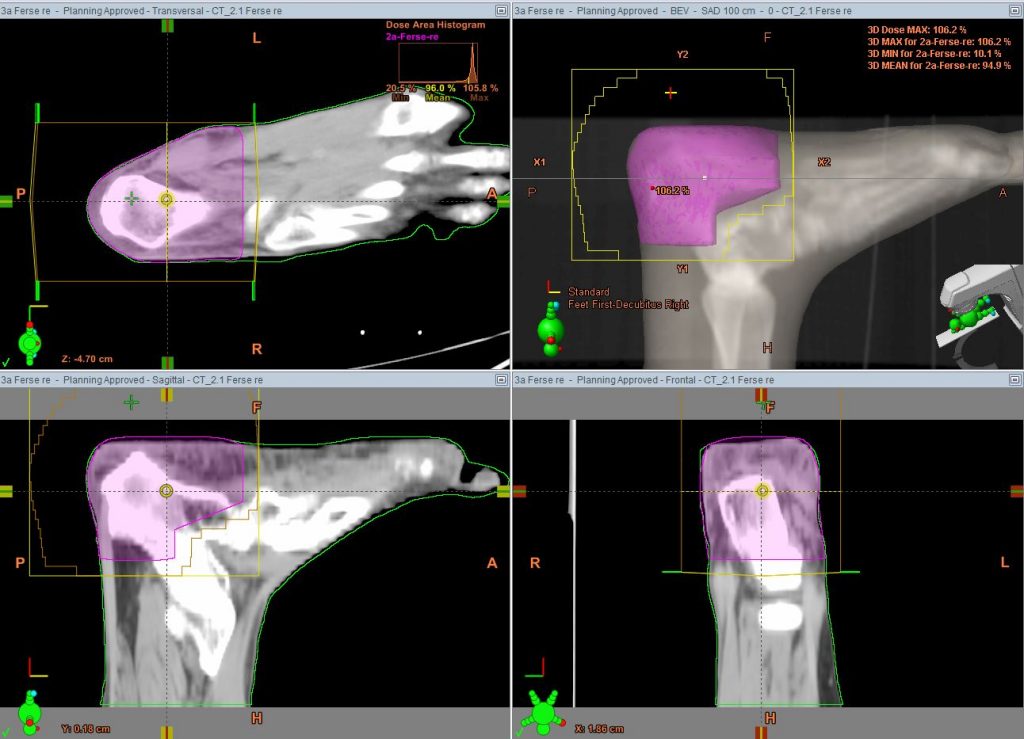

Bestrahlung gutartiger Erkrankungen

Eine geringere Zahl unserer Patienten leidet an gutartigen Erkrankungen, die mit dieser Methode symptomatisch behandelt werden. Dazu gehören […]